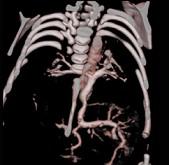

问题 女性,21岁,活动后呼吸困难,时常发生上呼吸道感染,CT扫描如图所示,请选择正确的选项 ( )

选项 A、该病人肺静脉异位引流入下腔静脉 B、该病人为心下型肺静脉异位引流 C、肺静脉异位引流根据引流肺静脉支数的不同可分为部分性及完全性 D、根据引流部位不同分为心上型、心脏型、心下型 E、考虑为肺静脉异位引流

答案 ABCDE